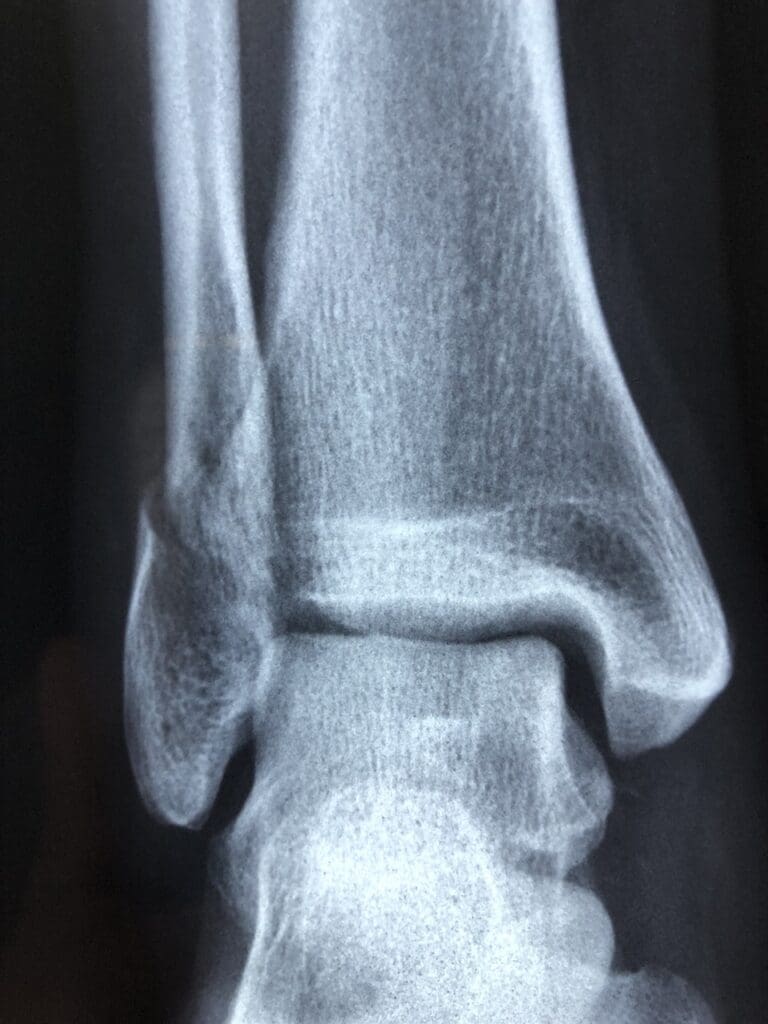

While most ankle sprains can be treated at home with rest, ice, compression, and elevation (RICE), there are some cases where medical attention may be necessary. If you experience the following symptoms after an ankle injury, it’s important to seek medical help:

- Severe pain and swelling

- Inability to bear weight on the affected ankle

- Persistent numbness or tingling

- Visible deformity or misalignment

If you suspect a severe ankle sprain or fracture, it’s best to seek medical attention to receive proper diagnosis and treatment.